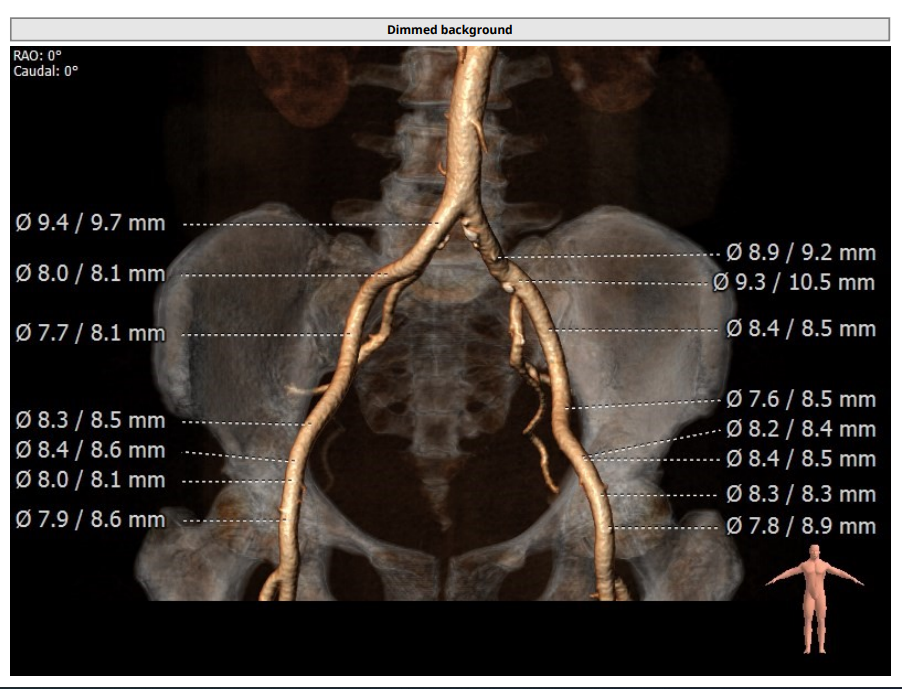

术前周浩教授带领团队对这位患者进行了详细的分析,从CT分析结果显示,患者的瓣环直径为25.1mm,结合患者瓣叶钙化等情况,符合美敦力Evolut PRO 29mm瓣膜选型要求。难点在于患者左右瓣叶钙化严重,钙化积分达到了1500,经讨论决定术中进行23mm球囊预扩张,保证系统顺利跨瓣及释放。术中采用了全球领先的Cusp Overlap瓣膜植入技术,实现更精准地定位瓣膜深度,减少对患者传导系统的影响。